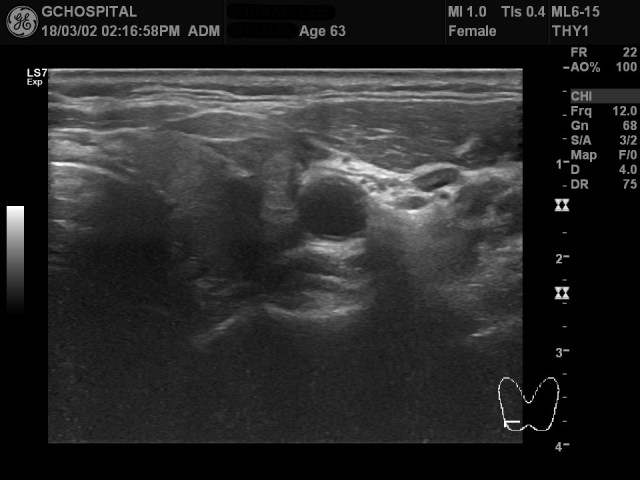

갑상선 좌엽에 있는 결절부위에 세침흡입생검을 실시하는 동안 얻은 영상입니다. 실제 생검을 시행하는 동안 결절이 굉장히 딱딱해서 생검바늘이 쉽게 들어가지도, 빠지지도 않았었습니다. 위 영상에서처럼 결절 내부에서 calcification 부위 근처에 위치해 생검을 한 결과, 하시모토 갑상선염으로 진단되었습니다.

하시모토갑상선염은 대부분 갑상선이 전반적으로 단단하고 커지면서 갑상선호르몬 수치는 떨어지는 hypothyroidism을 일으키는 질환입니다. 그런데, 약 5%의 경우에서는 정상적인 thyroid parenchym을 배경으로 이번 사례처럼 결절형태로 발현되는 경우가 있습니다.

이렇게 결절형태로 발현되는 경우 에코나 형태, 내부의 석회화 여부는 다양하기 때문에, 특정 패턴이 진단에 도움이 되는건 아니지만, 갑상선염을 배경으로 하는 결절형 하시모토 갑상선염의 경우에는 좀 더 등에코(isoechoic)에 딱딱한 결절형태로 나오는 경우가 더 흔하다고 합니다.

결절형 하시모토 갑상선염은 전체 하시모토 갑상선염의 5%정도에 불과하다고 하지만, 하시모토 갑상선염 자체가 갑상선질환들 중에서는 매우 흔한 질환 중 하나이기 때문에, 위와 같이 갑상선결절 내부에 후방에코음영을 보이는 경우에는 비록 macrocalcification이라고 해도 세침흡입생검을 고려할 필요가 있다고 생각합니다.

어떤 논문에서는 이런 결절형 하시모토갑상선염이 하시모토갑상선염의 초기형태라고 주장하는 경우가 있습니다. 그래서인지는 몰라도, 이런 결절형태에서는 갑상선호르몬 수치들이 정상인 경우가 흔하고, 이번 사례에서도 나중에 확인해보니, 갑상선호르몬 수치는 모두 정상이었습니다.